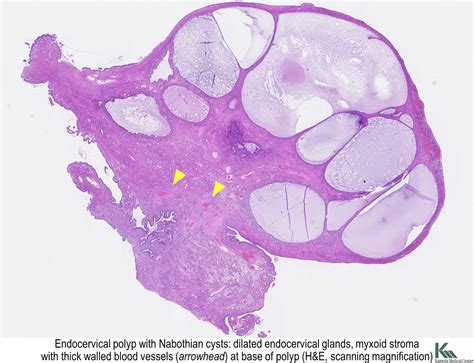

Visual aids can be incredibly helpful in understanding medical conditions. Cervical polyp pictures provide a clear view of what these growths look like. They can help patients recognize the signs and symptoms and understand the diagnosis process better. Below is a table that describes what cervical polyp pictures typically show:

Cervical polyp pictures are often used in medical textbooks and online resources to educate patients and healthcare providers about the appearance and characteristics of these growths. They can also be useful for comparing symptoms and seeking medical advice.